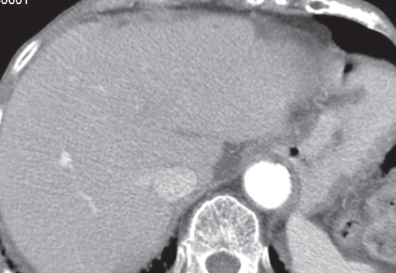

Betsy Phillip, PA-C; Ishak Mansi, MD

A 52-year old white woman with past medical history of right lower extremity deep venous thrombosis, hypertension, asthma, and degenerative joint diseases in both knees and cervical spines, presented to...